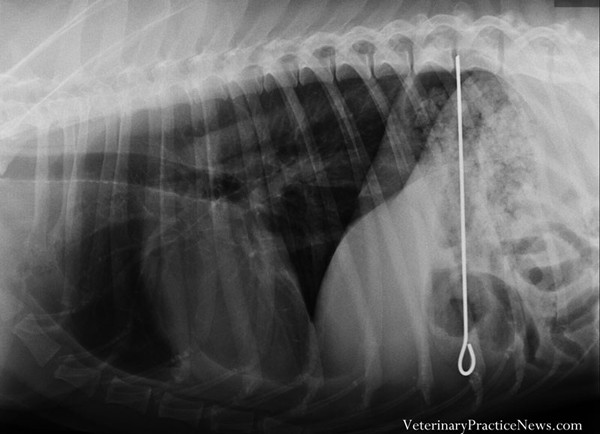

| Một chú chó nuốt nguyên một thanh sắt nướng thịt. |